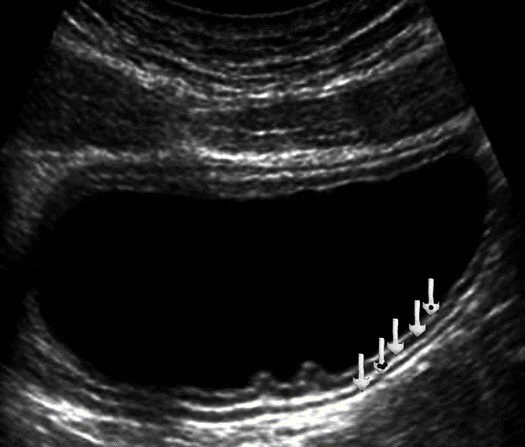

In the area of the body all the gastric wall layers are clearly differentiated. The gastric wall thickness when filled with the fluid does not exceed 3 mm (Figure 3). During peristaltic waves, there is also thickening of the gastric wall, which disappears after a few seconds. The greatest wall thickness of 3-5mm is observed in the antrum part. A careful monitoring illustrates the opening and closing of the pyloric canal (Figure 4).

Figure 3.Ultrasonography of the stomach body. The arrows show all layers of the stomach wall in the transverse section